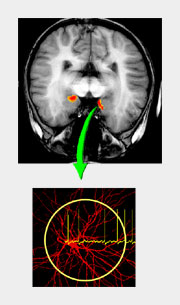

Im Rahmen des Sonderforschungsbereiches untersuchten Wissenschaftler die Grundlagen von Funktionen und Dysfunktionen der limbischen Strukturen des Gehirns. Die limbischen Schaltkreise des Gehirns übernehmen eine wichtige Vermittlerrolle, zum Beispiel zwischen bewussten und unbewussten Aktivitäten oder zwischen rationalen und emotionalen Komponenten bei bestimmten Verhaltensreaktionen.